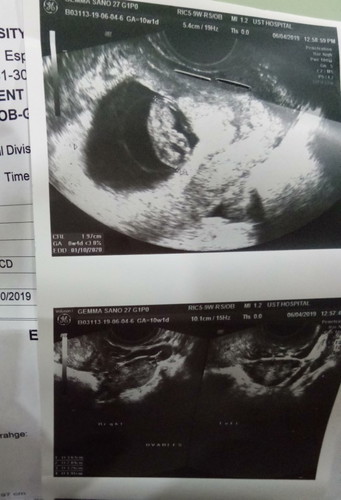

girl or boy?

Mga mars sa tingin nyo po ba girl or boy baby ko?

Wait 20 weeks to know best. Di nyo pa malalaman gender until then